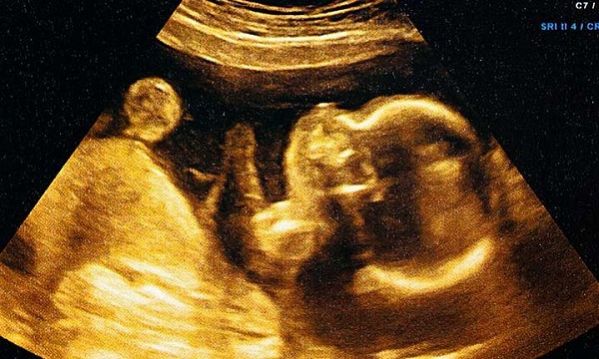

Είναι αλήθεια! Τα μωρά χαμογελούν με την γαλήνη και την αγάπη που παίρνουν. Δεν είναι λίγες οι φορές που αυτό έχει φανεί σε διάφορους υπερήχους, με μωρά να χαμογελούν από την 26η εβδομάδα της κύησης.